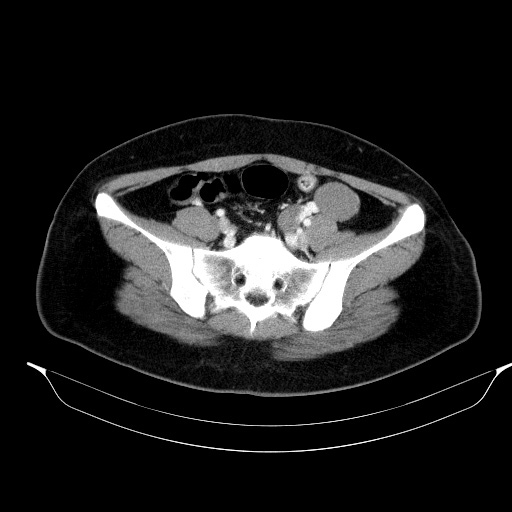

조영증강 전 영상에서 병변의 위쪽과 아랫쪽의 감쇄도(attenuation)가 다름을 알 수 있습니다.

조영증강 후 영상에서 각 부위에서 뚜렷한 조영증강은 보이지 않았습니다.

초음파영상에서 보였던 낭성병변은 CT에서는 하행결장과 뚜렷하게 떨어져 있었기에 duplication cyst는 배제할 수 있으며, lymphangitic cyst의 가능성도 떨어져 보입니다. 해당 병변은 Lt. adnexal region에 있는 병변으로 생각됩니다.

조영증강이 되지 않고, 초음파에서 무에코음영을 보인 부분은 단순낭종으로 생각할 수 있습니다. 초음파영상에서 약간의 에코음영이 보였던 부위는 조영증강이 되지 않은 대신 균일한 연부조직음영을 보여 낭종 내에 출혈 가능성을 배제하기 어려웠습니다.